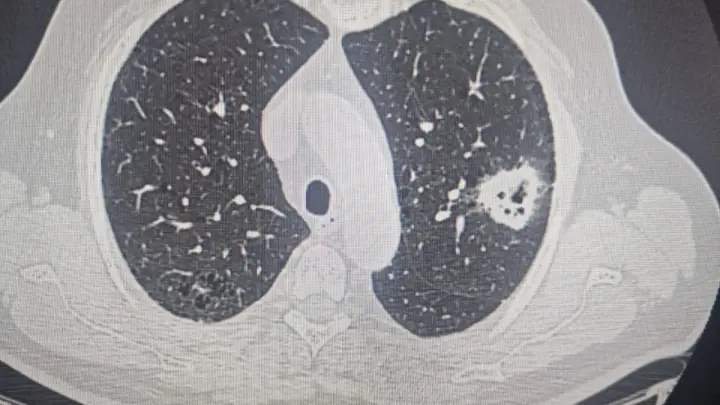

Новосибирские онкологи трижды прооперировали пациента с разными опухолями

Больному дважды диагностировали рак лёгких.

Врачи Новосибирского онкодиспансера поделились необычной историей спасения пациента, которого им пришлось оперировать трижды – дважды у него диагностироали рак лёгких и один раз заболевание поразило щитовидную железу. Историю приводит Минздрав Новосибирской области.

Как рассказал врач-онколог торакального отделения Вадим Козлов, первые симптомы заболевания проявились у пациента три года назад, когда выяснилось, что у него центральный рак правого легкого. Обычно в таком случае удаляют целое легкое, но новосибирские онкологи пошли другим путём, применив метод бронхоангиопластической верхней лобэктомии. Операция позволила сохранить пациенту большую часть легкого, удалив только поражённую ткань и восстановив бронхи и сосуды.

Через год после первой операции врачи обнаружили новообразование в левом легком. Удалось повторно провести вмешательство, сохранив оба лёгких пациента. Третья операция была проведена на щитовидной железе, так как параллельно была выявлена опухоль и в этом органе.

"Благодаря тому, что мы первый раз ему сохранили правое легкое, у нас была возможность оперировать на левом. Технически выполнить операцию на единственном легком невозможно. Если мы его отключим, то дышать пациенту будет нечем", — пояснил Вадим Козлов.

Третья операция, как и вторая, была выполнена щадящим методом — через проколы, что позволило пациенту быстрее восстановиться и вернуться к нормальной жизни.

По словам доктора, современные методы диагностики и хирургии позволяют лечить пациентов даже с распространёнными формами рака, улучшая продолжительность и качество их жизни. При этом особый акцент делается на профилактику и раннюю диагностику, поскольку в большинстве случаев поздняя стадия заболевания диагностируется у пожилых людей с сопутствующими заболеваниями, что усложняет лечение.